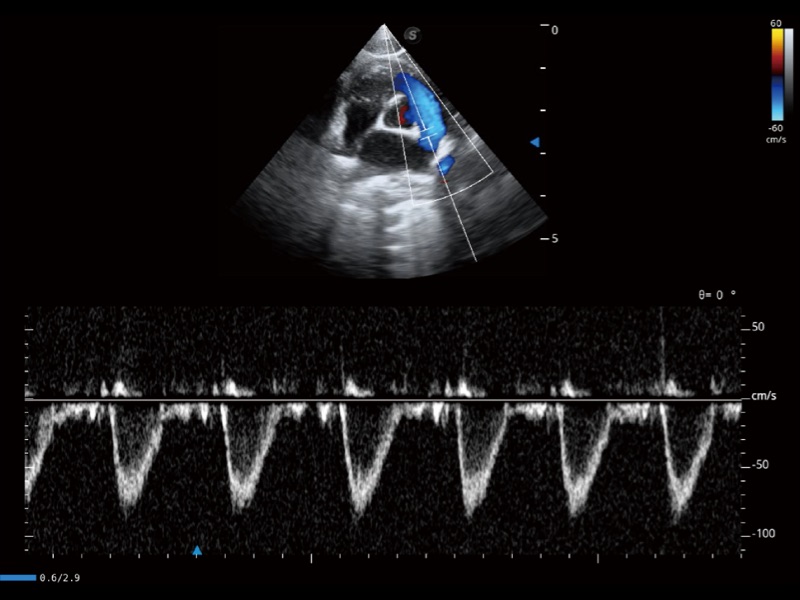

能够基于左心室壁追踪和辛普森法,自动计算射血分数,支持多个可移动点描迹,与手动测量相比,极大节省了动物医生的时间和精力。

通过360度任意调节3条M型取样线,在同一心动周期上观察心脏不同位置的运动曲线,得到准确的心功能测量数据,有效评估心肌运动及左心室功能。